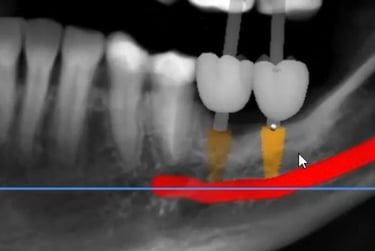

Comparação do Planejamento com o Resultado

Aspecto Tomográfico Final do Enxerto e Planejamento Digital para o Implante

Pouco osso? A cirurgia guiada pode ser a solução.

Mesmo quando há pouca quantidade de osso, muitas vezes não é preciso fazer enxerto.

Com o uso de tecnologia digital em 3D, a cirurgia guiada permite planejar com precisão milimétrica a posição dos implantes, aproveitando ao máximo o osso disponível.

Esse planejamento detalhado também possibilita desviar de estruturas importantes, como o canal mandibular (por onde passa um nervo sensível) e o seio maxilar (uma cavidade natural próxima aos dentes superiores), tornando o procedimento mais seguro e previsível.

Caso da cirurgia guiada dispensando o enxerto - Imagens originais — nenhuma contém retoques